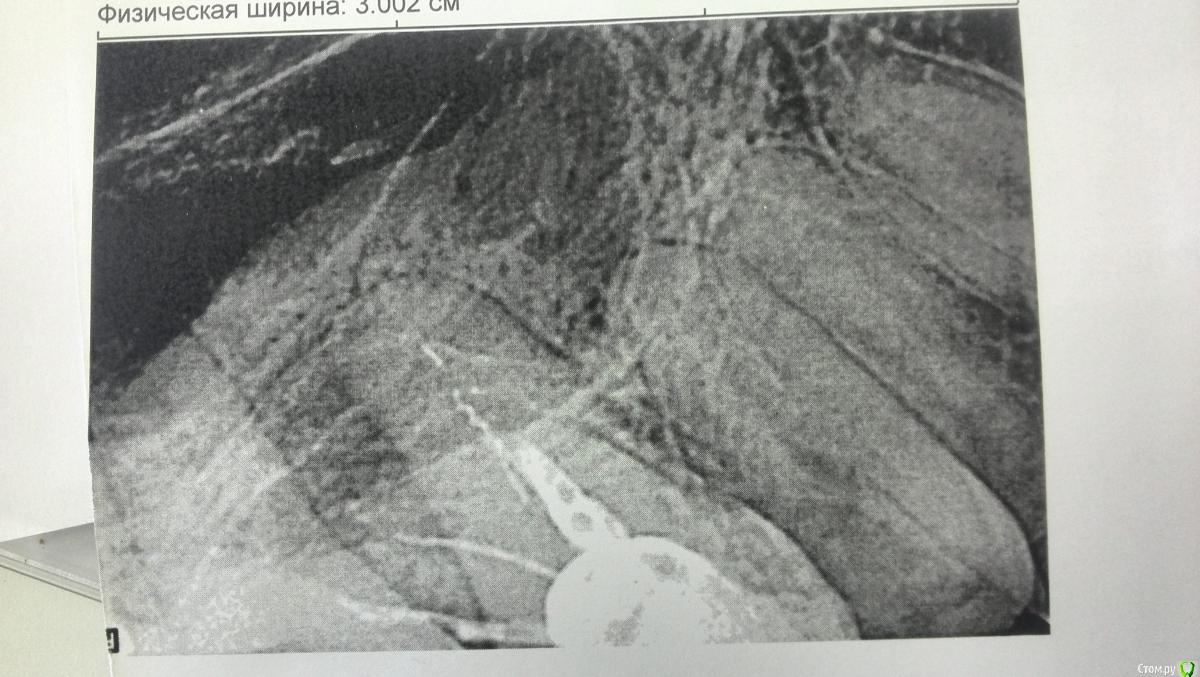

Снимок 11. На этом снимке, сделанном в процессе лечения другого зуба, врач случайно увидел гранулему (крайний правый зуб) и сказал, что она возникла из-за того, что один из каналов абсолютно пустой, не запломбирован. К слову, лечение пульпита в этом зубе проводилось 20 лет назад. Зуб не беспокоил, но врач заверил, что его необходимо перелечить.

post-55146-0-14499200-1526837188_thumb.jpg